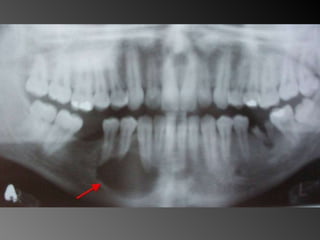

Granuloma (Lesão) Periférico de Células Gigantes A excisão cirúrgica deve ser antecedida de exame radiográfico, pois lesão não completamente removida e/ou com infiltração óssea, pode recorrer

Granuloma (Lesão) Periféricode Células Gigantes A excisão cirúrgica deve ser antecedida de exame radiográfico, pois lesão não completamente removida e/ou com infiltração óssea, pode recorrer

26 - Pacientedo sexo feminino, 30 anos de idade, se apresentou com aumento de volume no corpo da mandíbula, região dos dentes 45, 46 e 47, assintomático e com evolução de aproximadamente 1 ano. Pelo exame clínico constatamos expansão óssea e deslocamento dos dentes 45 e 46 de suas posições normais. Através de radiografia panorâmica observamos uma imagem radiográfica multilocular onde as trabéculas ósseas se encontravam perpendicularmente umas às outras e em outras regiões com aspecto de bolha de sabão. Com base no quadro clínico, o diagnóstico é: a) Ceratocisto e mixoma odontogênico. b) Odontoma composto e ameloblastoma. c) Mixoma odontogênico e ameloblastoma. d) Mixoma odontogênico e odontoma composto. e) Ameloblastoma e ceratocisto.

Exame complementares RadiografiaPanorâmica; Radiografia Oculsal; Teste de Vitalidade; Punção Exploratória; Biópsia incisional.

Teste de VitalidadeDente 43: Negativo Dentes 42,44 e 45: Positivo.